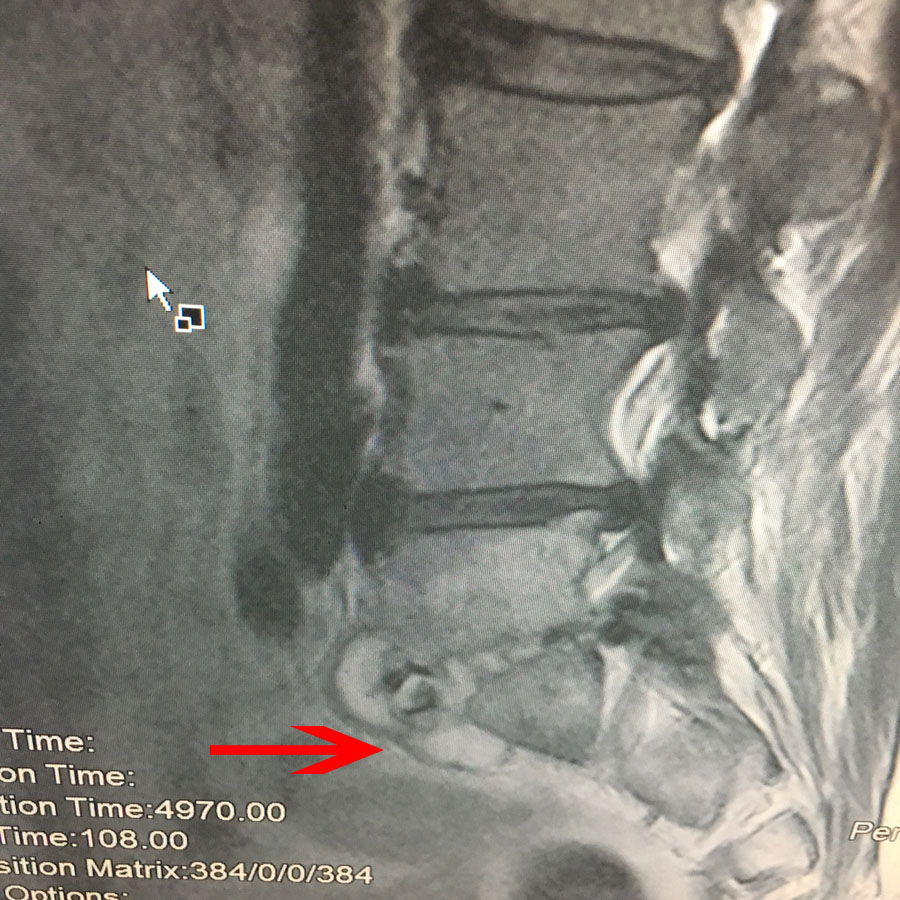

Ωστόσο λίγες μέρες αργότερα διαπιστώθηκε επιδείνωση του πόνου του γι’ αυτό και επανεισήχθει, οπότε έγινε εκ νέου έλεγχος της Ο.Μ.Σ.Σ. με μαγνητική τομογραφία.

- ζ

Εικ 4 – Μαγνητική Τομογραφία ΟΜΣΣ α,β Μετωπιαία (Coronal) Λήψη γ,δ Οβελιαία (Sagittal) λήψη – Ακολουθία Τ1-Τ2 , ε,στ,ζ Εγκάρσια (Axial) λήψη – Ακολουθία Τ2

Παρατηρείται αυξημένη προ και περισπονδυλική ιστική αντίδραση.